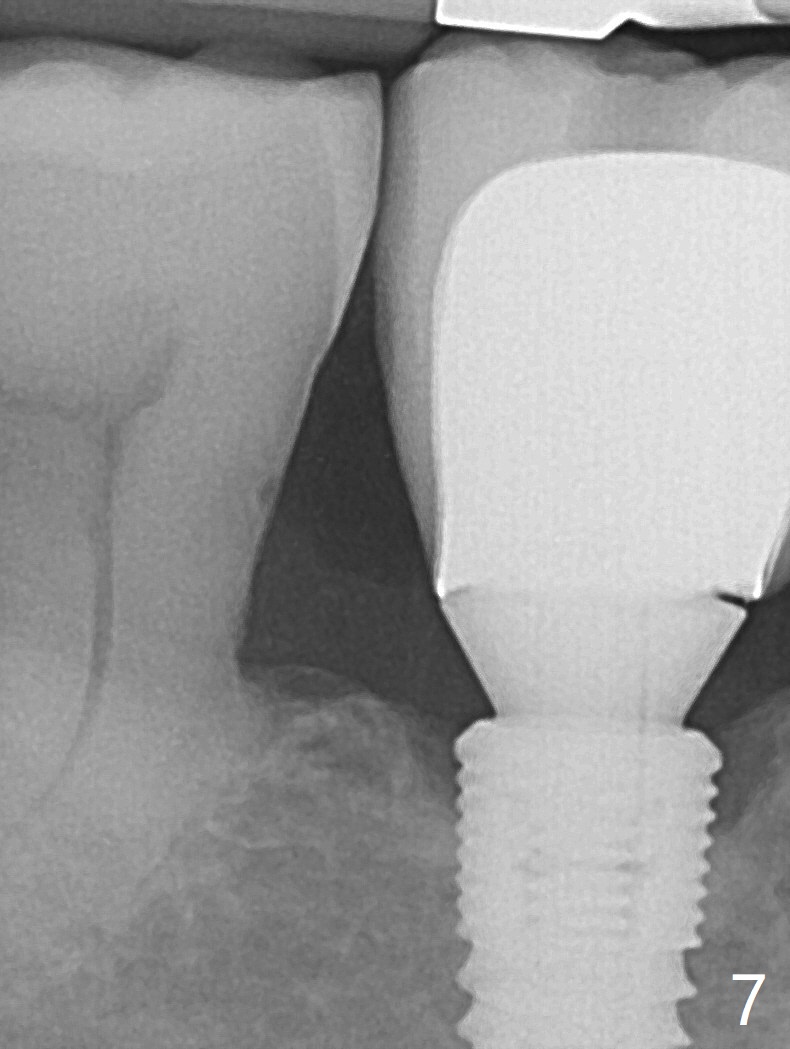

开场白病例

74岁男